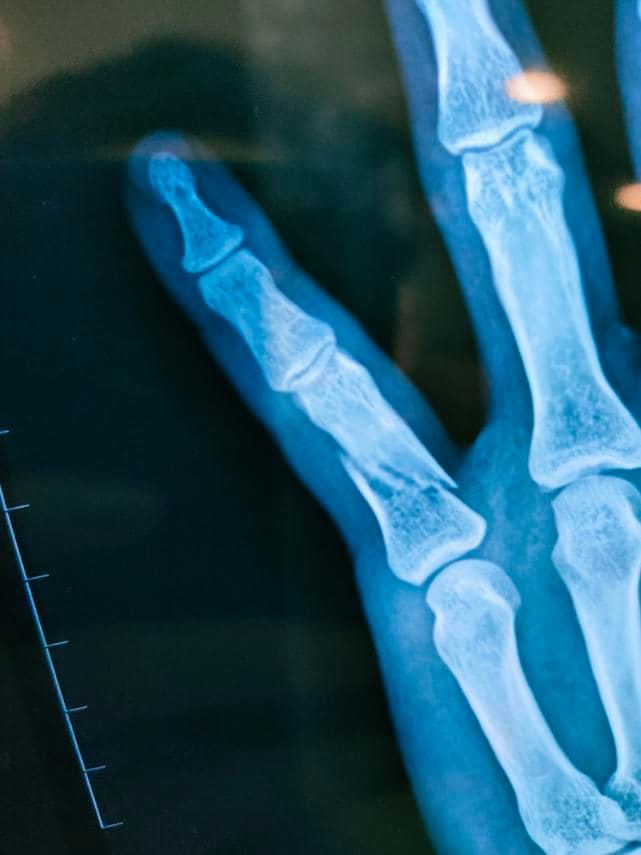

Cụ thể, quản lý truyền thông của Isaac đã có những chia sẻ như sau: “Chuyện giờ mới kể. Trong lần quay hình bị tai nạn, xương tay gãy đôi nhưng lịch trình biểu diễn đã lên lịch từ lâu nên Isaac vẫn đi diễn và hóa trang cẩn thận. Chỉ có vệ sĩ đi theo biết để bảo vệ lúc khán giả xô đẩy không va trúng cái tay. Thấy ảnh (Isaac) nhảy tưng tưng và cái tay được bao lại kĩ nên vệ sĩ không tin, nhưng thiệt là sau khi nhảy và xô đẩy, vào xe xong là ảnh ôm tay kêu đau quá, lúc diễn hay trước khán giả không bao giờ than, diễn như chưa hề có việc gì cả, nể thiệt chứ. Hôm nay đã bắt đầu được nghỉ tết nên mới dám tiết lộ.

Cám ơn các anh chị bầu show, nhãn hàng đã chia sẻ hỗ trợ Isaac trong tai nạn bất đắc dĩ này. Xin lỗi mọi người vì Isaac bắt tay mọi người bằng một tay và luôn giấu tay phải sau lưng (tay phải bị thương, chụp chế độ selfie sẽ bị ngược lại). Xin lỗi mọi người vì bao nhiêu họp báo, show, hẹn hò, tiệc tùng đều hạn chế vì vác cái tay đi lại khá khó khăn bất tiện, không cầm được đũa kể cả mặc áo. Tin mừng là bác sĩ đã cho tháo bột ăn Tết dù vẫn phải để ý cẩn thận“.